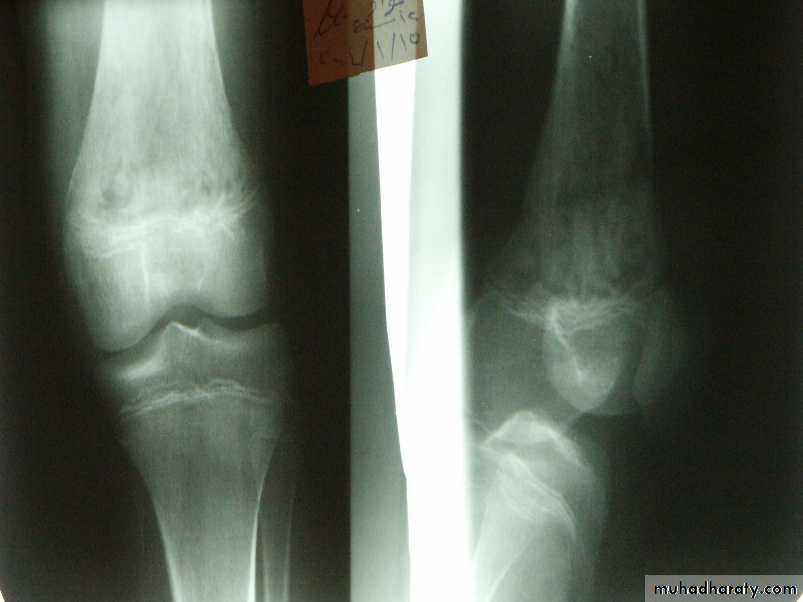

The most common site is the metaphysis of the long bone particularly around the knee joint.

X-ray finding:

x-ray films are negative within 1-2 weeks,Although carefully comparison with the opposite side may show abnormal soft tissue shadows.

It must be stressed that x-ray appearances are normal in the acute phase. There are little value in making the early diagnosis.

Radiography not appear till after 3 weeks.

decrease bone density moth eaten.later on new bone formation.